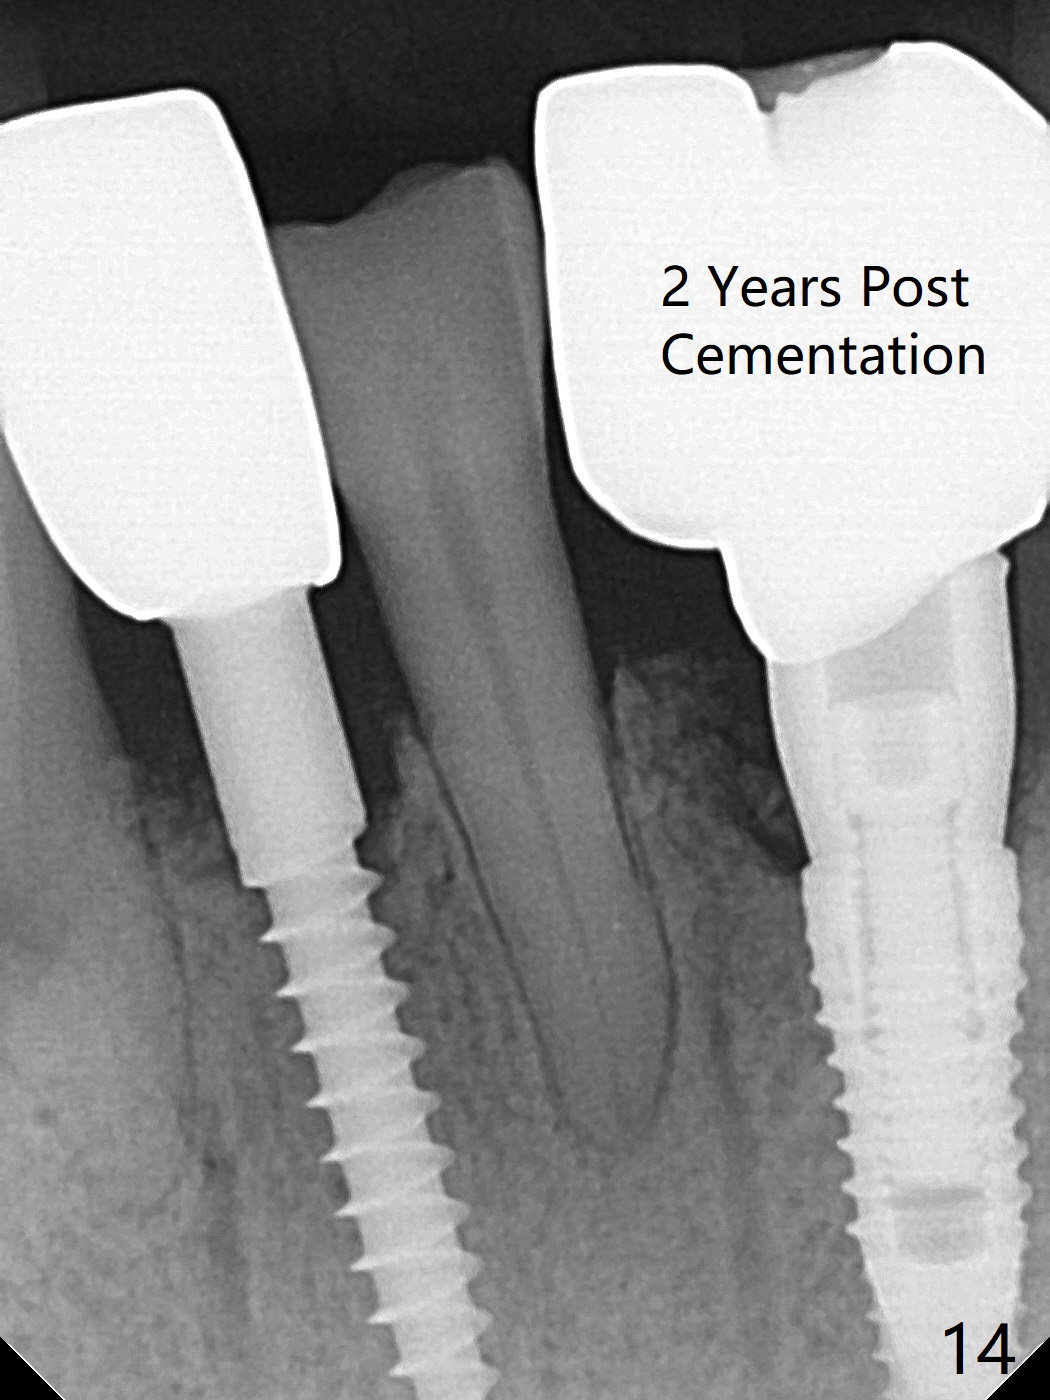

There is a fistula buccal to the apex of the tooth #23 preoperatively (Fig.1), which is related to loss of the buccal plate of the socket of #23. Therefore an implant is placed mainly in the socket of #22 (Fig.3). The lingual (Fig.2 L) gingiva appears to have more extensive inflammation. After extraction, the lingual (Fig.3 L) gingival margin is significantly lower than the buccal one. The lingual crest is ~ 4 mm lower than the buccal one. A 3.8x10 mm dummy implant is placed tentatively with an apical space (Fig.4). When a same dimension definitive implant is placed with 40 Ncm, it is 2 mm below the lingual gingival margin, whereas 6-7 mm below the buccal one (Fig.5). Vanilla graft is placed before placement of a 5.5x4(5) mm abutment (Fig.6,7). There is a 2-3 mm lingual (L) gap to be filled with the allograft secondarily to prevent periimplantitis (Fig.7). Later the abutment is changed to a longer and smaller one (Fig.8) with more of the allograft (*). After trimming of the abutment (Fig.9 (*: papilla between the fused teeth)), an immediate provisional is fabricated to close the socket (Fig.10, similar to Fig.1). The majority of the bone graft seems to be in place 8 months postop (Fig.12). The implant appears to have been placed buccal, consistent with the thin and slightly erythematous buccal gingiva (Fig.13). The ridge completely regenerates 2 years post cementation (Fig.14).